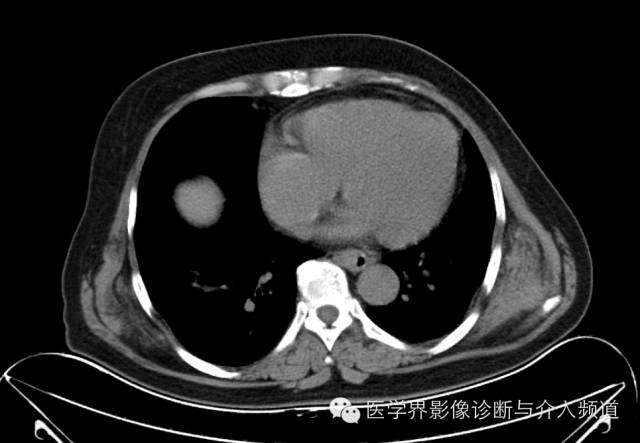

男性,45岁,体力劳动者,主因偶发无痛性肿块,近期肿块增大,伴局部不适入院,行CT检查。

双侧肩胛骨内侧前锯肌下可见梭形软组织密度肿块,与肌肉密度类似,肿块内部密度不均匀,其内可见条索状低密度影,前锯肌受压外移,病变与周围结构分界清晰。

弹力纤维瘤

根据软组织肿瘤的世界卫生组织分类标准,弹力纤维瘤属于成纤维细胞/肌成纤维细胞肿瘤中的良性肿瘤;背部肩胛下角附近是其好发部位,且右侧多发,可能与EFD发病原因有关(肩胛骨与胸壁摩擦增加,右侧活动较多),但一侧发病时也应留意对侧;病变一般呈扁平椭圆形,生长缓慢,大部分临床无症状。

在组织学上,EFD主要由胶原纤维和弹力纤维构成,纤维组织有明显透明变性,纤维细胞较少,弹力纤维分散于纤维组织中,瘤组织内看见灶性脂肪细胞。大部分学者认为其不是一种真性肿瘤,而是反应性增生。

CT平扫时EFD密度与肌肉相当,其内索条状脂肪间隔将其分隔成纤维状,增强扫描轻度强化或无明显强化,此病是影像学即可诊断的疾病之一。